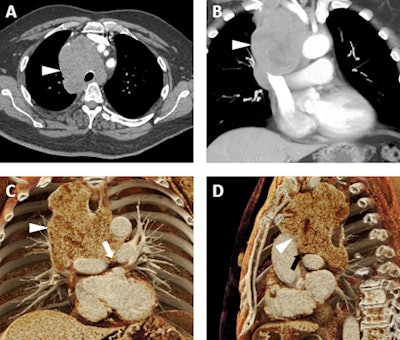

A 66-year-old man with a known diagnosis of pulmonary large cell neuroendocrine tumor. A: Axial postcontrast 2D CT image demonstrates a confluent lymph node mass (white arrowhead) occupying much of the superior mediastinum with encasement of the trachea and interdigitation among multiple vascular structures. B: Volume-rendered image also demonstrates the mass (white arrowhead), which abuts and/or narrows the superior vena cava, the innominate veins, the aorta, and major arterial branches arising from the aortic arch, and the main, left, and right pulmonary arteries. C and D: Cinematic-rendered visualizations; the photorealism of these renders allows for the depiction of the tumor infiltrating between the left and right pulmonary arteries (white arrow in C) and between the ascending aorta and left pulmonary artery (black arrowhead in D). While this patient was not a surgical candidate, the added detail from cinematic rendering relative to other 3D techniques may prove quite valuable in surgical planning in regions of complex vascular anatomy. All images courtesy of Drs. Steven Rowe, Pamela Johnson, Elliot Fishman, and the British Journal of Radiology.For regions of complex anatomy, cinematic rendering is likely to be of great value to both diagnostic imaging specialists and vascular interventionalists who are determining patient treatment plans, according to Rowe, an assistant professor of radiology at Johns Hopkins University in Baltimore. Furthermore, the cinematic-rendered images can facilitate patient education and informed consent by making disease processes easier to visualize and understand.